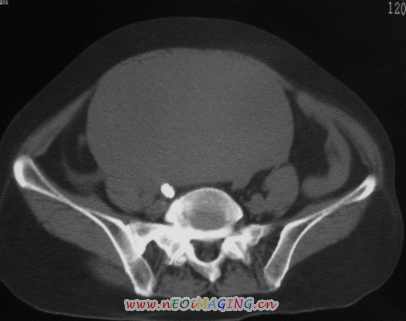

标题: CT11527:女56岁以右输尿管结石入院

女56岁以右输尿管结石入院

病灶位于下腹部盆腔,从子宫与膀胱明显受压后移看,应该来源于盆腹腔的占位,病灶实性部分密度均匀,左侧可见低密度灶,建议增强扫描,考虑:间叶性肿瘤,或硬纤维瘤,输尿管下段结石伴上段输尿管扩张

支持卵巢囊腺瘤;右侧输尿管第二狭窄处结石伴梗阻。

1)盆腔占位性病变,考虑来源于卵巢,囊腺瘤可能性大。2)右侧输尿管第二狭窄处结石伴梗阻。

今天病人已经手术证实为右附件囊肿,右侧输尿管第二狭窄处结石伴梗阻!!!

[病理诊断] CT11527:右附件囊肿,右侧输尿管结石。